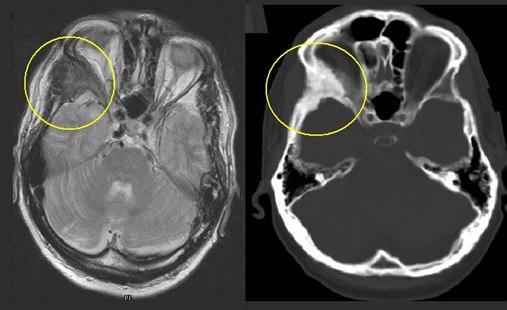

Det hyppigste stedet hvor forandringene opptrer er i ansiktsskjelettet. Dette kan føre til synlige skjevheter eller kuler. Forandringene kan også oppstå på undersiden av skallen og kan da trykke på ryggmarg og nerver fra ryggmargen. Dersom det oppstår forandringer i legger eller lår er det økt risiko for brudd og feilstillinger.

Diagnostikk

Forandringene kan noen ganger ses som kuler i ben - i ansiktet eller andre steder på kroppen. Andre ganger kan forandringene påvises ved røntgen-undersøkelse i forbindelse med smerter eller plager. Som regel vil det være nødvendig med en vevsprøve for sikkert å fastslå diagnosen. Gentest kan også brukes.